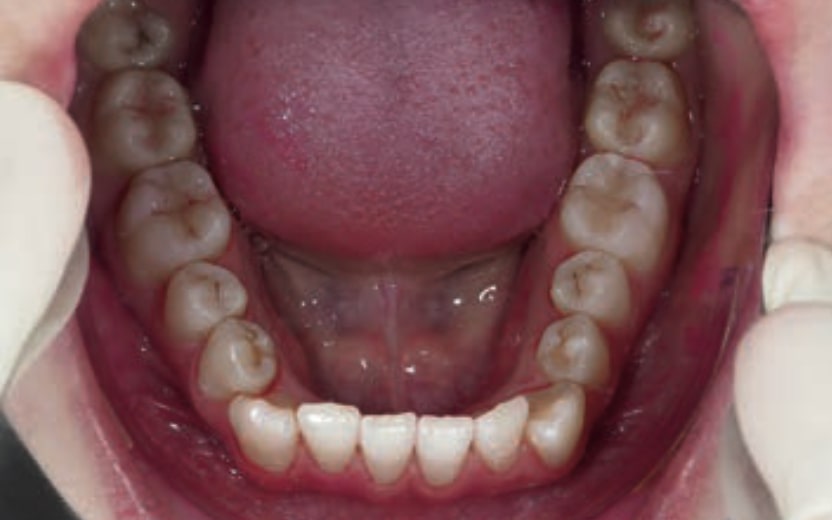

Chief complaint: The patient, a 19-year-old woman, was evaluated to undergo orthodontic treatment using the Angel Aligner Pro system. She presents with a skeletal Class III, mesofacial, with a dental Class III malocclusion and a 2 mm deviation of the lower midline to the left. Teeth 33 and 43 are out of the arch and cortical bone, with a crossbite issue on tooth 33. Fortunately, no functional issues affecting swallowing or breathing have been detected. The patient’s motivation for starting treatment was a general review of her dental and aesthetic health. The soft tissue analysis reveals mandibular protrusion that influences her facial profile. This diagnosis highlights the need for a comprehensive approach to address dental and skeletal misalignments, improving both the patient’s functionality and facial aesthetics.

• Dental Class III, 2 mm deviation of the lower midline to the left. 33 and 43 out of the arch and the cortical bone.

• Crossbite of 33.